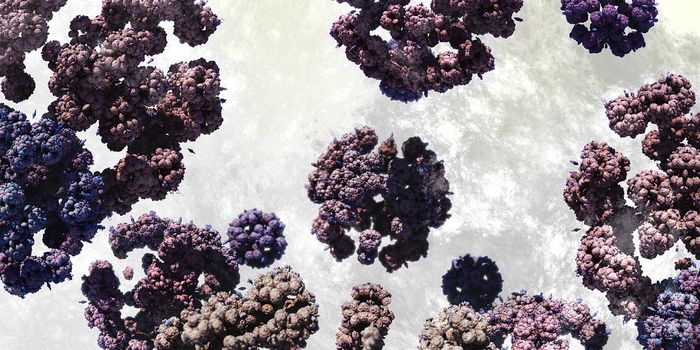

MAY 28, 2015ImmunologyA phase III clinical trial has demonstrated the therapeutic benefit of the oncolytic virus Talimogene Laherparepvec (T-V ...